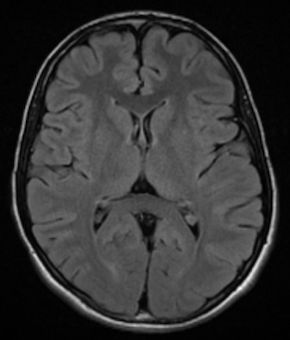

Figure 1

Our patient was admitted for 16 days and discharged home with mild cognitive delays but no activity restrictions. After discharge, the patient had close follow-up with neurology and hematology/oncology, including a 2nd dose of rituximab and a repeat MRI that showed interval complete resolution of previously identified T2-weighted-fluid-attenuated inversion recovery hyperintensity within pulvinar region of bilateral thalami. He was given a 504 plan for additional time in academic activities, however reports not using it and is earning B’s in school.

Figure 3